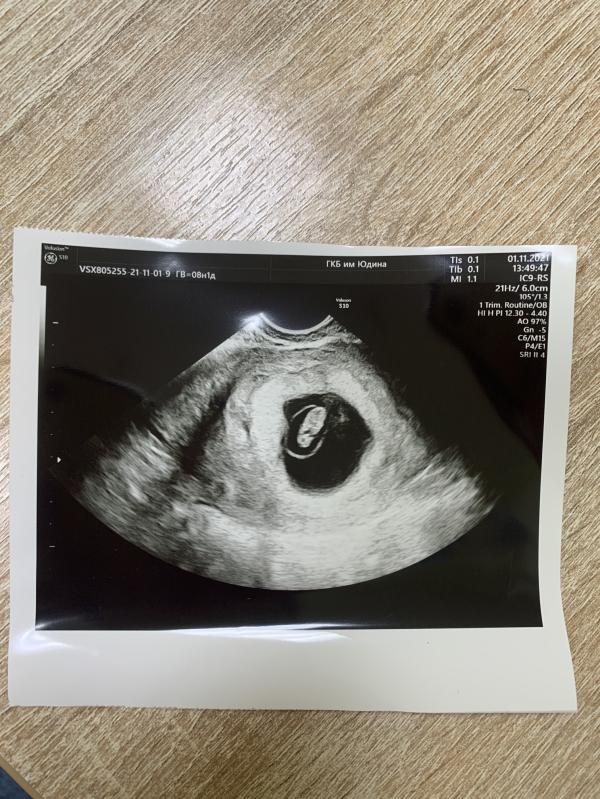

post image

Девочки, кто делал узи на сроке 6-7-8 недель, покажите ☺️ так интересно посмотреть. Мне сделали вчера. 7 недель 1 день